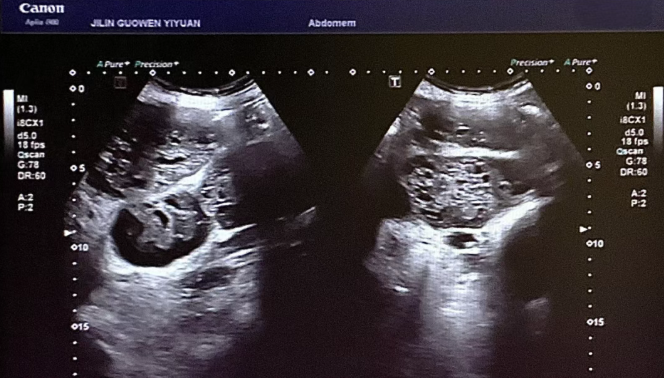

患者錢女士(化名),65 歲,因有高血壓病史而定期進(jìn)行體檢。在超聲檢查時,醫(yī)生發(fā)現(xiàn)其腎臟存在占位性病變。超聲科團(tuán)隊借助高分辨率超聲成像技術(shù),清晰地觀察到腎臟內(nèi)的異;芈晠^(qū),再結(jié)合血流信號分析,高度懷疑該病變可能為惡性腫瘤。為進(jìn)一步明確診斷,團(tuán)隊在超聲引導(dǎo)下進(jìn)行精準(zhǔn)穿刺,獲取病理組織。最終,病理報告確診該病變?yōu)?“小圓細(xì)胞惡性腫瘤”。

小圓細(xì)胞惡性腫瘤是一類較為少見的惡性疾病,常見于兒童及青少年,而發(fā)生在老年患者腎臟的情況則更為罕見。此類腫瘤具有很強(qiáng)的侵襲性,早期診斷對于治療方案的制定以及患者的預(yù)后都至關(guān)重要。錢女士雖然沒有出現(xiàn)典型癥狀,腹部查體也未觸及包塊,但得益于超聲科的細(xì)致檢查,病灶被及時發(fā)現(xiàn),這為后續(xù)的治療贏得了寶貴時間。